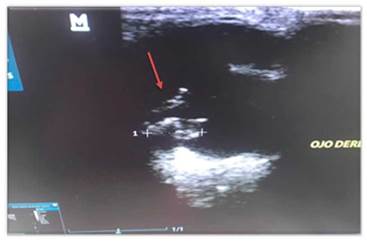

En la ecografía ocular se evidencia masa en cuerpo ciliar derecho de 0,92 por 0,52 cm, no se observa infiltración de masa en cámara vítrea, o anormalidad en retina, ni desplazamiento de cristalino. Se lleva a cabo extracción de humor acuoso, y se envía muestra para citología a laboratorio Corpavet (Figura 5 y 6). Los resultados citológicos confirman depósitos de gránulos de pequeño tamaño, uniformes, negruzcos, compatibles con pigmento melánico y agrupados. Los hallazgos citológicos son morfológicamente compatibles con melanoma (Figura 7). Posteriormente se realiza patología confirmando por laboratorio Corpavet, el diagnóstico fue melanoma uveal (Figura 8), la citología ocular se realizó antes de la enucleación.

De acuerdo a lo anterior, en el ojo derecho del paciente, se observa gracias a la ecografía, una masa con una densidad heterogénea, bien definida en el cuerpo ciliar derecho (Figura 14), insinuante de una neoplasia a nivel uveal, como diagnóstico.